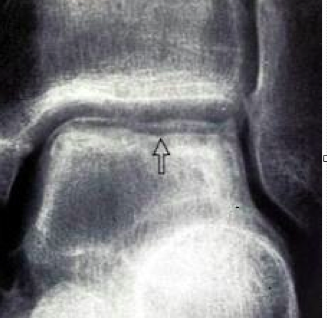

What is your landmark to determine talar neck or talar body

lateral process